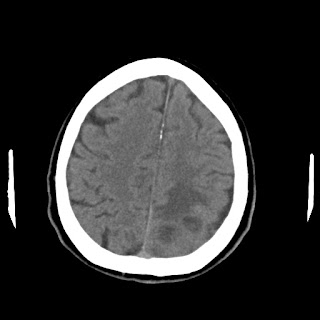

Caso neurorradiología

Paciente de 60 años con cuadro de 1 semana de evolución consistente en tropiezos frecuentes y alteración en la movilidad del miembro

inferior derecho. No refiere

cefalea u otros síntomas asociados, no pérdida de peso, no náuseas o emesis, no

sudoración nocturna. Antecedentes de hipertensión arterial y diabetes.

Escanografía